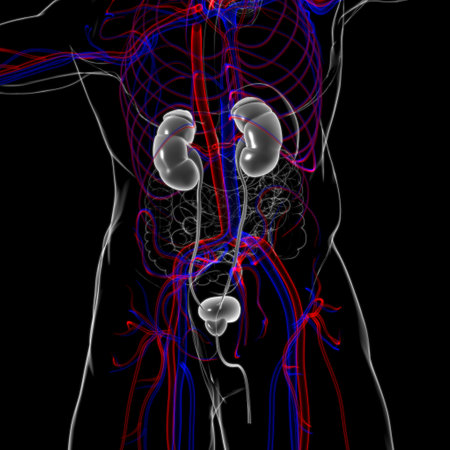

Human kidneys and circulation with a skeleton medical diagram

Human Urinary System Kidneys with Bladder Anatomy For Medical Concept 3D Illustration

Human Urinary System and Kidneys Anatomy

Human Urinary System Kidneys with Bladder Anatomy For Medical Concept 3D Illustration

Human Urinary System Kidneys with Bladder Anatomy For Medical Concept 3D Illustration

3D Illustration Concept of Female Urinary System Kidneys Anatomy

Human Urinary System Kidneys with Bladder Anatomy For Medical Concept 3D Illustration

3D Illustration Concept of Human Urinary System Kidneys Anatomy

3D Illustration Concept of Human Urinary System Kidneys Anatomy

3D Illustration Concept of Human Urinary System Kidneys with Bladder Anatomy